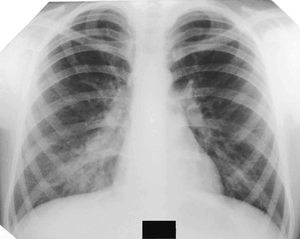

Важным этапом постановки диагноза остаётся отличие её от других заболеваний лёгких, коронавируса. Так, при бронхите будет отсутствовать затемнение на снимке, вместо этого — усиление лёгочного рисунка.

Усиление лёгочного рисунка

В случае присутствия инородного тела, наблюдается затемнение с чёткими краями, локализующееся в нижней доле лёгкого. Спутать с воспалением типичного характера сложно.

При плеврите, на снимке скопление экссудата в поражённой области. Плеврит выступает в качестве осложнения недолеченной пневмонии.

При пневмотораксе присутствует характерный уровень жидкости. На снимке отображается как просветление, лёгочный рисунок не просматривается.